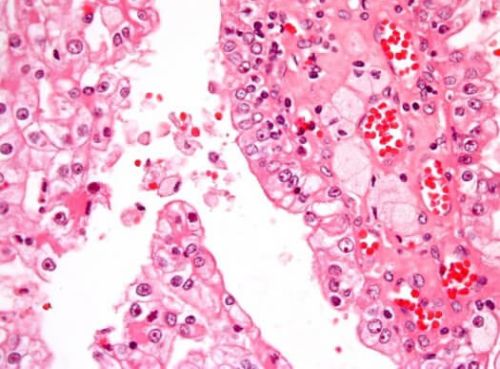

Nowotwór pojawia się, gdy złośliwe komórki mnożą się poza kontrolą w ciele. Rak nerki u dzieci najczęściej przyjmuje formę guza Wilmsa, inaczej nerczaka zarodkowego. Tworzy się w niedojrzałej tkance nerkowej. Pomimo pojedynczego uszkodzenia, może wpływać na obie nerki. Jest to przypadek znany jako obustronny guz.